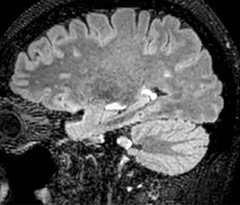

Improving scan time and/or spatial resolution

A two year follow-up scan of a CPA meningioma using both Ingenia 3.0T without CS and Ingenia Elition 3.0T with Compressed SENSE allows for a nice comparison to demonstrate the protocol improvements achieved on the Elition: 3D FLAIR has a shortened scan time, improved SNR and still the same spatial resolution. BrainView (3D T1 TSE) has improved spatial resolution and SNR with shortened scan time. For 3D T2 Drive the spatial resolution has been improved. 3D THRIVE used to have an interpolated 0.8 mm slice thickness, but true thickness at 1.6 mm, so that axial slices displayed a decent quality, but reformats were suboptimal. Compressed SENSE is used on Elition to improve spatial resolution and reduce the non-interpolated slice thickness to allow smoothly reformatted images. Total scan time (adding SmartBrain and an additional b2000 diffusion) was 13:19 on Ingenia, and is now reduced to 10:42 on Ingenia Elition.

Ingenia 3.0T (without Compressed SENSE)

3D FLAIR 1.0 x 1.0 x 1.0 mm* 4:24 min.

3D TSE T1w 1.0 x 1.0 x 1.2 mm* 2:40 min.

3D T2w Drive 0.8 x 0.8 x 1.0 mm* 3:05 min.

3D T1w THRIVE 0.8 x 0.8 x 1.6 mm* 1:30 min.

Ingenia Elition 3.0T with Compressed SENSE

3D FLAIR 1.0 x 1.0 x 1.0 mm* 2:50 min.

3D TSE T1w 1.0 x 1.0 x 1.0 mm* 2:10 min.

3D T2w Drive 0.7 x 0.7 x 0.7 mm* 2:52 min.

3D T1w THRIVE 0.7 x 0.7 x 0.8 mm* 1:30 min.

*true voxel size, without interpolation